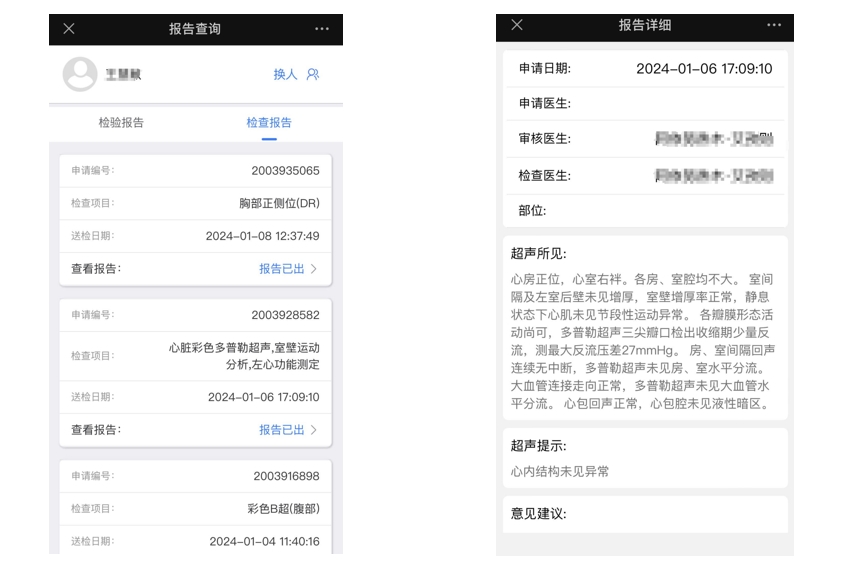

实体医院线上预约挂号系统源码,主要面向大中型的医院机构,适用于各级公立和民营医院用来搭建互联网医院平台,可对接院内his、lis、pacs系统。多家三甲医院应用案例。

一款服务于三甲医院的预约挂号系统,它集合了预约挂号、预约记录、在线支付、医保支付、医保信息、电子报告、住院金预交、住院每日清单查看等功能模块。